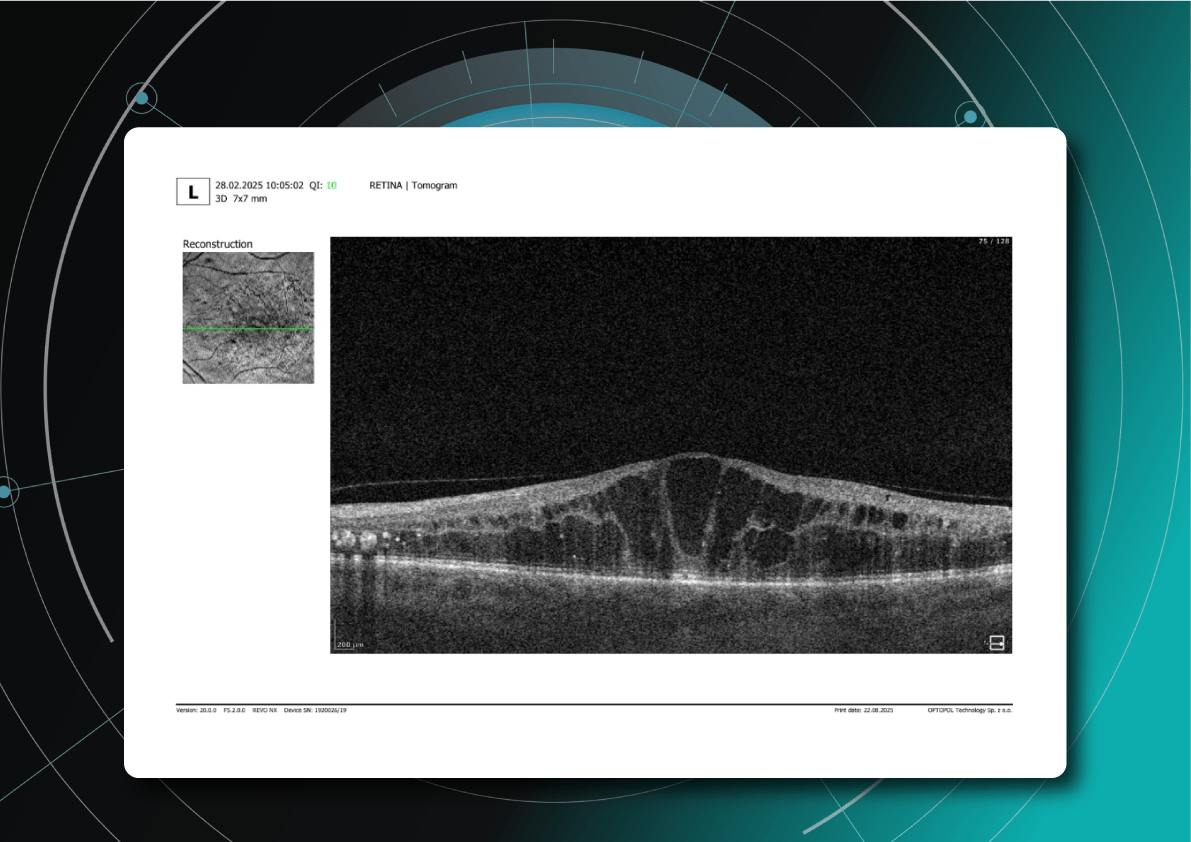

For instance, AI today can assess the early risk of glaucoma based on the GCC asymmetry measurements. Here is how AI-powered OCT workflow would look.

AI-assisted readings of OCT scans are already helping not only with pathology detection but also with the analysis of its progression or response to treatment. This represents a new approach to monitoring, where practitioners no longer need to sift through various patient notes but can directly compare reports from previous examinations and observe how, for instance, shadowing has changed in micrometers.

Let’s explore how this applies to a clinical case, such as monitoring a patient with Wet AMD during follow-up visits.

Data demonstrates that OCT findings can reveal the onset or progression of neovascular AMD before a patient reports new symptoms or changes in visual acuity. In fact, OCT images are reported to have the best diagnostic accuracy in monitoring nAMD disease states. This underscores the importance of key OCT findings or biomarkers in personalizing anti-VEGF treatment, achieving disease control, and reducing monitoring burdens.

Central Retinal Thickness emerged as one of the earliest OCT biomarkers used as an outcome measure in clinical trials for nAMD.

However, due to confounding factors, CRT’s use in outcome-based assessments of nAMD varies. Thus, it is essential to evaluate additional morphological changes alongside retinal thickness and their relationships with functional outcomes.

It has been reported that OCT images have the best diagnostic accuracy in monitoring nAMD disease states.

Another finding that is correlated with a worsening VA due to the associated photoreceptor defects is any damage to the four outer retina layers, including the RPE, interdigitation zone (IZ), ellipsoid zone (EZ), and external limiting membrane band (ELM).

OCT is a valuable imaging tool for visualizing subretinal hyperreflective material (SHRM). It can automatically identify and quantify SHRM and fluid and pigment epithelial detachment to calculate the overall risk of worsening visual outcomes associated with SHRM.

Subsequent follow-up visits will then display the most relevant picture, highlighting the most pertinent biomarkers for tracking a particular pathology (wet AMD in our example) and comparing their volume, progression, or regression through visits.

Another helpful option is retinal layer segmentation, which focuses solely on the retinal layers of interest for the specific case.

This level of customization empowers clinicians with a comprehensive yet targeted view of the patient’s condition. It saves time from manually detecting anomalies on scans and facilitates informed decision-making and personalized treatment plans.